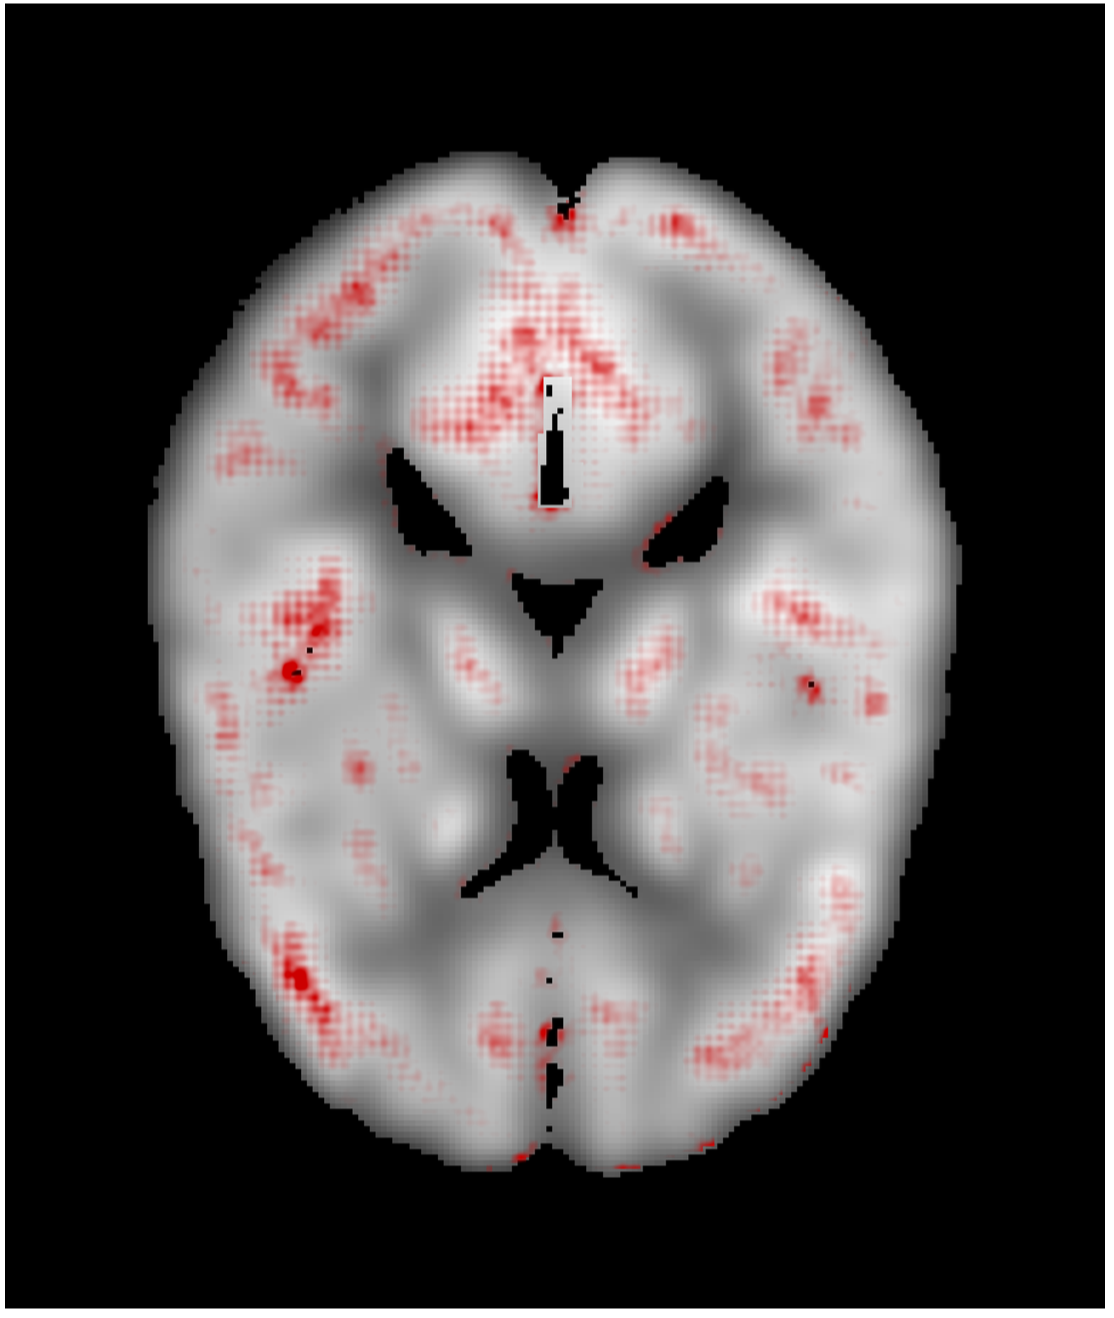

3.1 Visualization

We generated relevance heatmaps for all visualizations methods, averaged over AD PET images in the test dataset. Figure 2 presents the visual comparison of these five methods. The red areas/dots indicate that regions were important for the decision making of the 3D-CNN model. From the result, we can see that all the visualization focuses mostly on similar brain regions. There are some differences, such as the heatmaps generated for the gradient-based methods are distributed. The heatmaps highlight the areas that the CNN network is most susceptible. For the LRP method, the heatmap shows the average relevance of each voxel for contributing to the AD diagnosis score. The heatmaps generated by the occlusion based methods are more focused on the specific regions and cannot administer with large areas of distributed relevance. The reason behind the issue is the occlusion path was not able to cover those areas (for example, the cortex) completely. Brain area occlusion presents very high relevance for the temporal lobe. Since in this method, only one area is covered at a time, that can cause such high importance for one region and minimal relevance for other regions.

3.2 Impact of Brain Region

To evaluate the visualization result, we consider the literature available from the medical domain [16], [19], as there is no ground truth for validating the generated heatmaps. Table. 1 presents the top five most relevant regions for each visualization method. The relevance in each area following the AAL atlas was summed together to identify the most relevant areas for AD PET scans. From the top five relevant brain areas for each visualization method, we can see that the 3D-CNN focuses on the temporal lobe area, including the hippocampus for CN/AD classification. So, our findings are similar to those in the medical literature [16], [19].